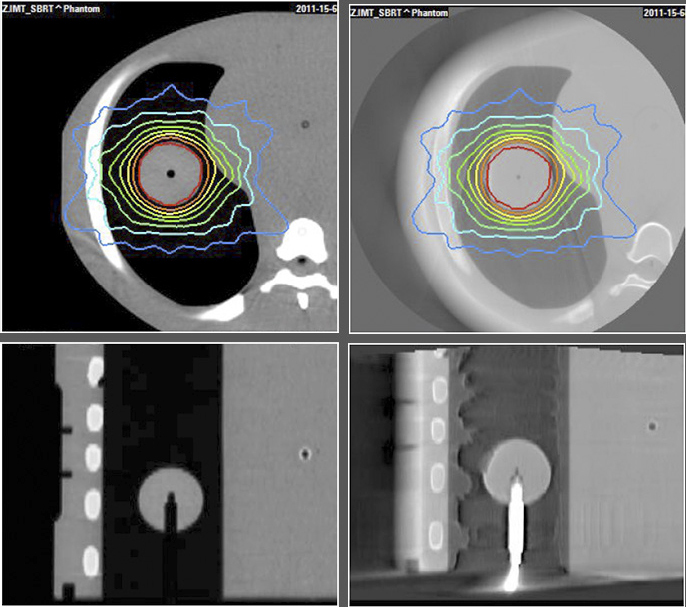

The End-to-End SBRT Phantom is a single tool for high-accuracy end-to-end commissioning and routine QA necessary for the high dose per fraction associated with SBRT deliveries.

Daily System Checks

The E2E SBRT Phantom contains multiple targets and alignment marks for verifying that imaging, localization, and targeting systems are aligned. This is a critical need for accurate delivery of these high-dose treatments.

OSL Dosimeters

Three OSL pockets in the right lung provide high-resolution dosimetry measurements to the target and spinal cord in a single delivery.